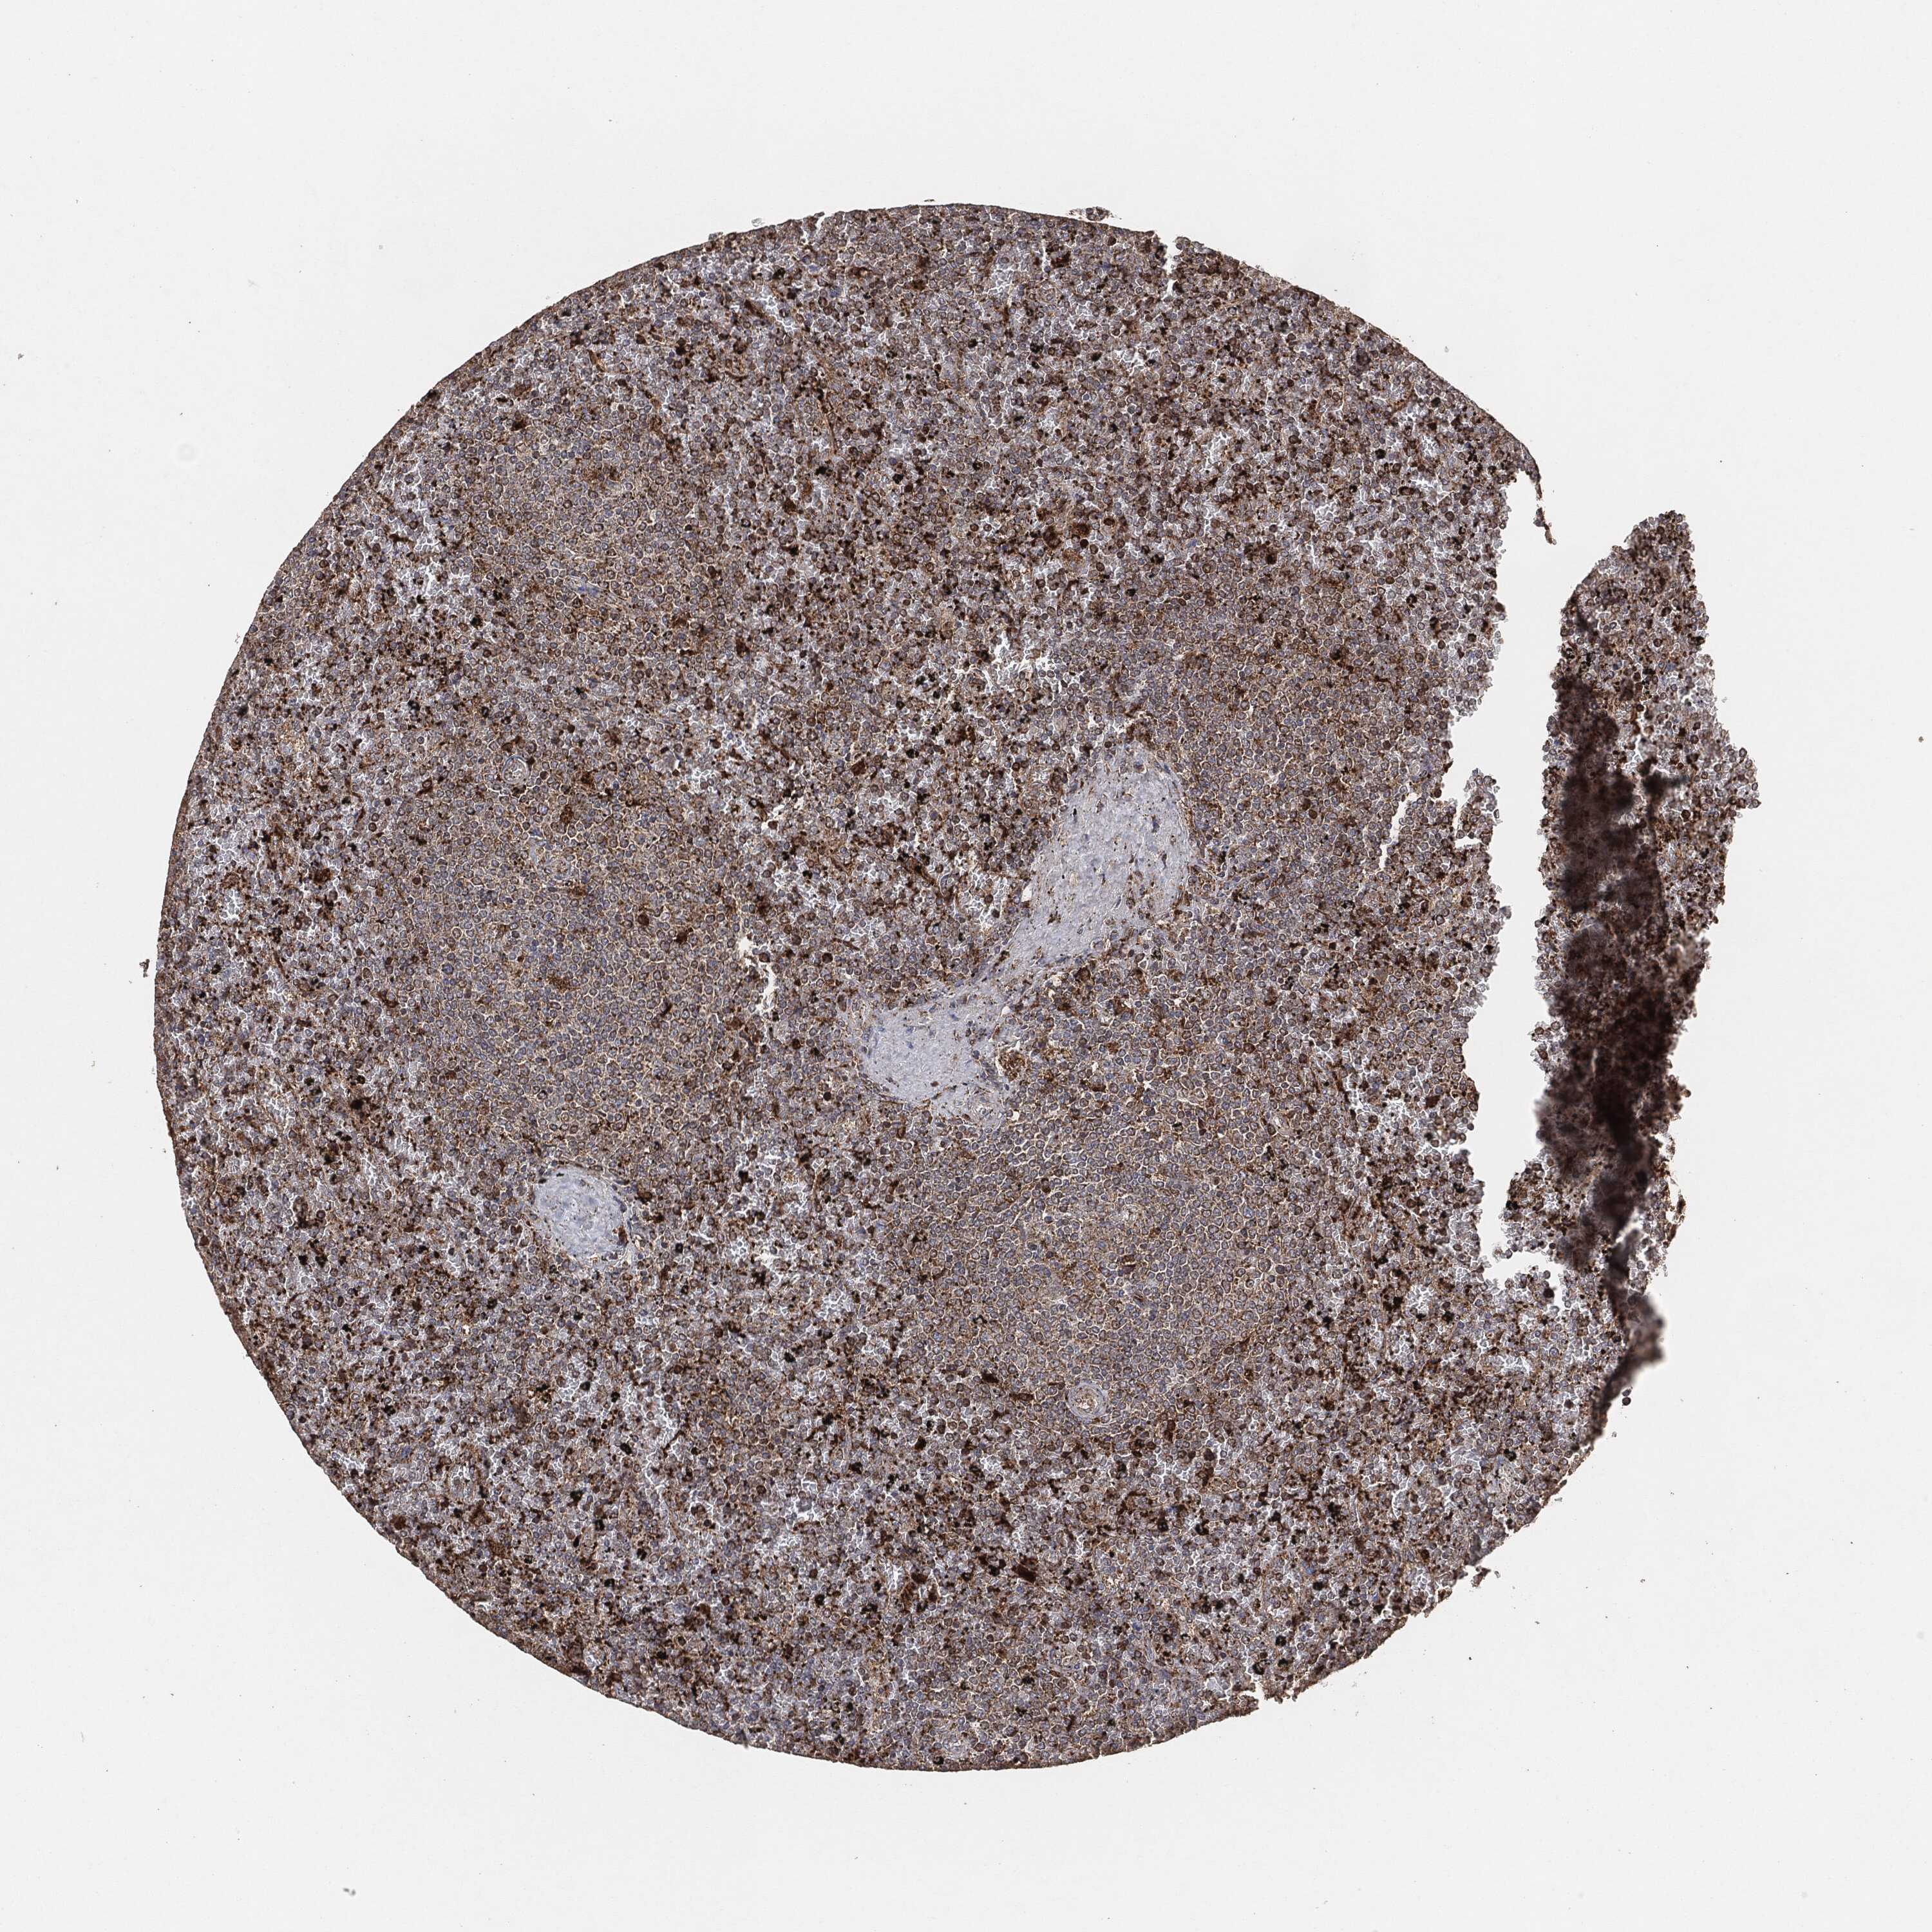

LYMPHOMA - Protein expressioni

A mouse-over function shows sample information and annotation data. Click on an image to view it in a full screen mode. Samples can be filtered based on level of antibody staining by selecting one or several of the following categories: high, medium, low and not detected. The assay and annotation is described here.

Antibody stainingi

Antibody staining in the annotated cell types in the current human tissue is reported as not detected, low, medium, or high, based on conventional immunohistochemistry profiling in selected tissues. This score is based on the combination of the staining intensity and fraction of stained cells.

Each image is clickable and will lead to virtual microscopy that enables deeper exploration of all samples and also displays staining intensity scores, fraction scores and subcellular localization as well as patient and tissue information for each sample.

Malignant lymphoma, non-Hodgkin's type, High grade

Hodgkin's disease, NOS

Malignant lymphoma, non-Hodgkin's type, Low grade